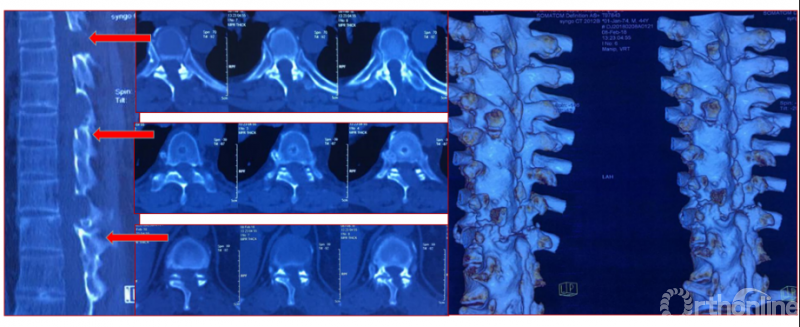

影像学资料

术中资料

同一侧一次两个节段减压,择期对侧进行两个节段减压,两侧腹侧减压范围可达到硬膜囊360度环形减压效果。术后复查硬膜囊环形减压效果。关节突关节破坏较多,需长期佩戴支具固定,保证术后脊柱稳定性。

术后复查资料